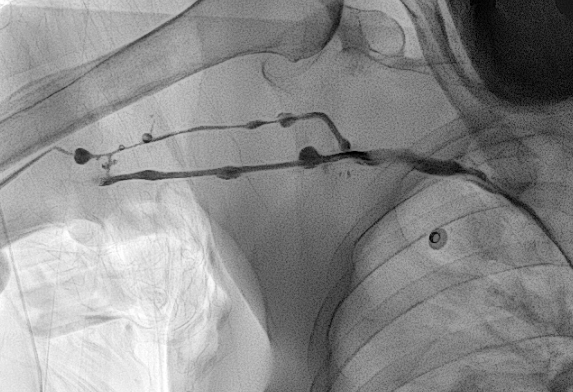

1. PICC 삽입 얼마나 걸려요?

PICC 삽입에는 그리 긴 시간이 소요되지 않습니다.

시술 자체는 3분 내지 5분이 걸립니다.

소독이 끝나고 시술자가 들어오고 나서는 대략 3분에서 5분 걸린다고 보시면 됩니다.

b. 혈관이 막혔거나 아주 좁은 경우

오랜 기간 동안 PICC 를 가지고 계셨거나, 독한 약물 치료를 받으신 분들 중에는 말초 정맥이 막혀버렸거나 아주 좁아져버린 분들이 계십니다. 이 경우 찔렀던 혈관을 그대로 이용하려면 풍선 카테터를 이용하여 혈관성형술을 하거나, 아니면 다른 혈관을 새로 찔러 들어가야 합니다. 두 해결 방법 모두 시간을 늘어지게 하는 방법이지요.